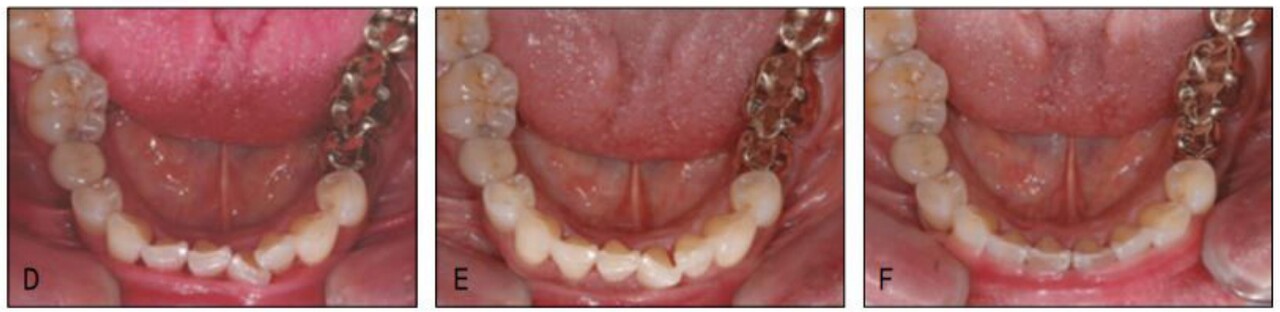

그러나 최근에는 불편감을 줄이기 위해 작은 크기(low profile)의 장치를 사용하고 동통을 줄이기 위해 미약한 힘(light force) 을 이용하는 테크닉들이 속속 개발되어 고령자 교정의 가능성 및 수월성이 크게 증가하였다. 수요의 증가에 맞는 교정치료 공급이 가능하게 된 바 고령자 교정은 폭발적으로 증가할 것으로 기대하고 있다.